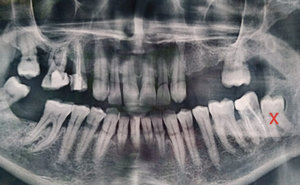

Нижняя правая восьмерка. Сам зуб не беспокоит, капюшон не мешает, но бывает из-под капюшона вытекает гной. Сказали надо удалять, но я что-то побаиваюсь, т.к. зуб целиком находится в костной ткани и близко к нижнечелюстному каналу.

Есть ли такая необходимость в его удалении, и насколько сложным и опасным оно будет?

Вам необходимо удалить все зубы мудрости. С 48 зубом рекомендую обратиться в ЧЛХ, так как Вы правы, корни данного зуба находятся в канале и после удаления продолжительное время у Вас будет парестезия (онемение). Но удалять крайне необходимо по причине того, что он повредит седьмой зуб, что в Вашем случае при отсутствии 46 будет очень нежелательно.